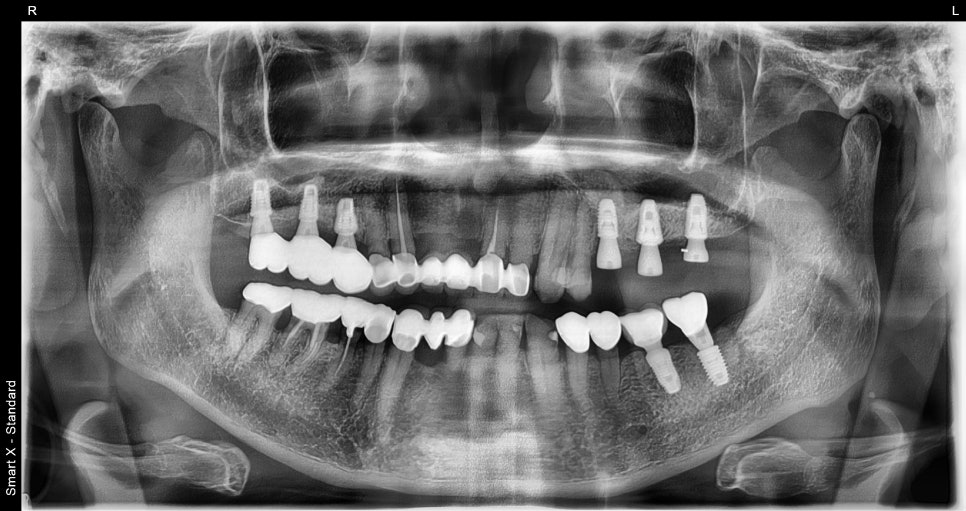

This panoramic X-ray was taken immediately after implant placement following extraction of #25.

It was placed neatly in alignment with the adjacent teeth.

Also, after removing the #26 and #27 implant crowns, they were safely replaced with buttons (healing abutments).